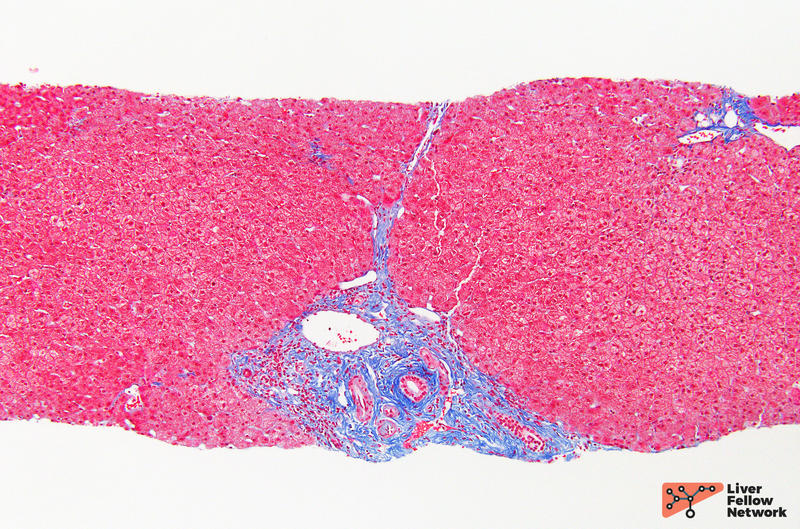

Masson trichrome stain showing bridging fibrosis and fibrotic expansion What Is Fibrous Portal Expansion fibrous portal expansion: fibrous tracts join branches of afferent portal veins and efferent hepatic veins, bypassing the hepatocytes and limiting their blood supply. top right—hvg stain showing steatohepatitis with mild fibrosis in the form of fibrous expansion (arrow) of the portal. fibrous portal expansion: Fibrous expansion of most portal areas, with or without short fibrous septa:. What Is Fibrous Portal Expansion.

What Is Fibrous Portal Expansion . top right—hvg stain showing steatohepatitis with mild fibrosis in the form of fibrous expansion (arrow) of the portal. fibrous portal expansion: fibrous tracts join branches of afferent portal veins and efferent hepatic veins, bypassing the hepatocytes and limiting their blood supply. fibrous expansion of portal areas, with marked bridging, portal to portal and portal to central 5 marked bridging with occasional nodules. fibrous portal expansion: Stage 0 (no fibrosis), stage 1 (fibrous portal expansion) ( figure 3 ), stage 2. Fibrous expansion of some portal areas, with or without short fibrous septa: Fibrous expansion of most portal areas, with or without short fibrous septa: Hence, fibrosis contributes both to hepatocyte ischemia (causing.